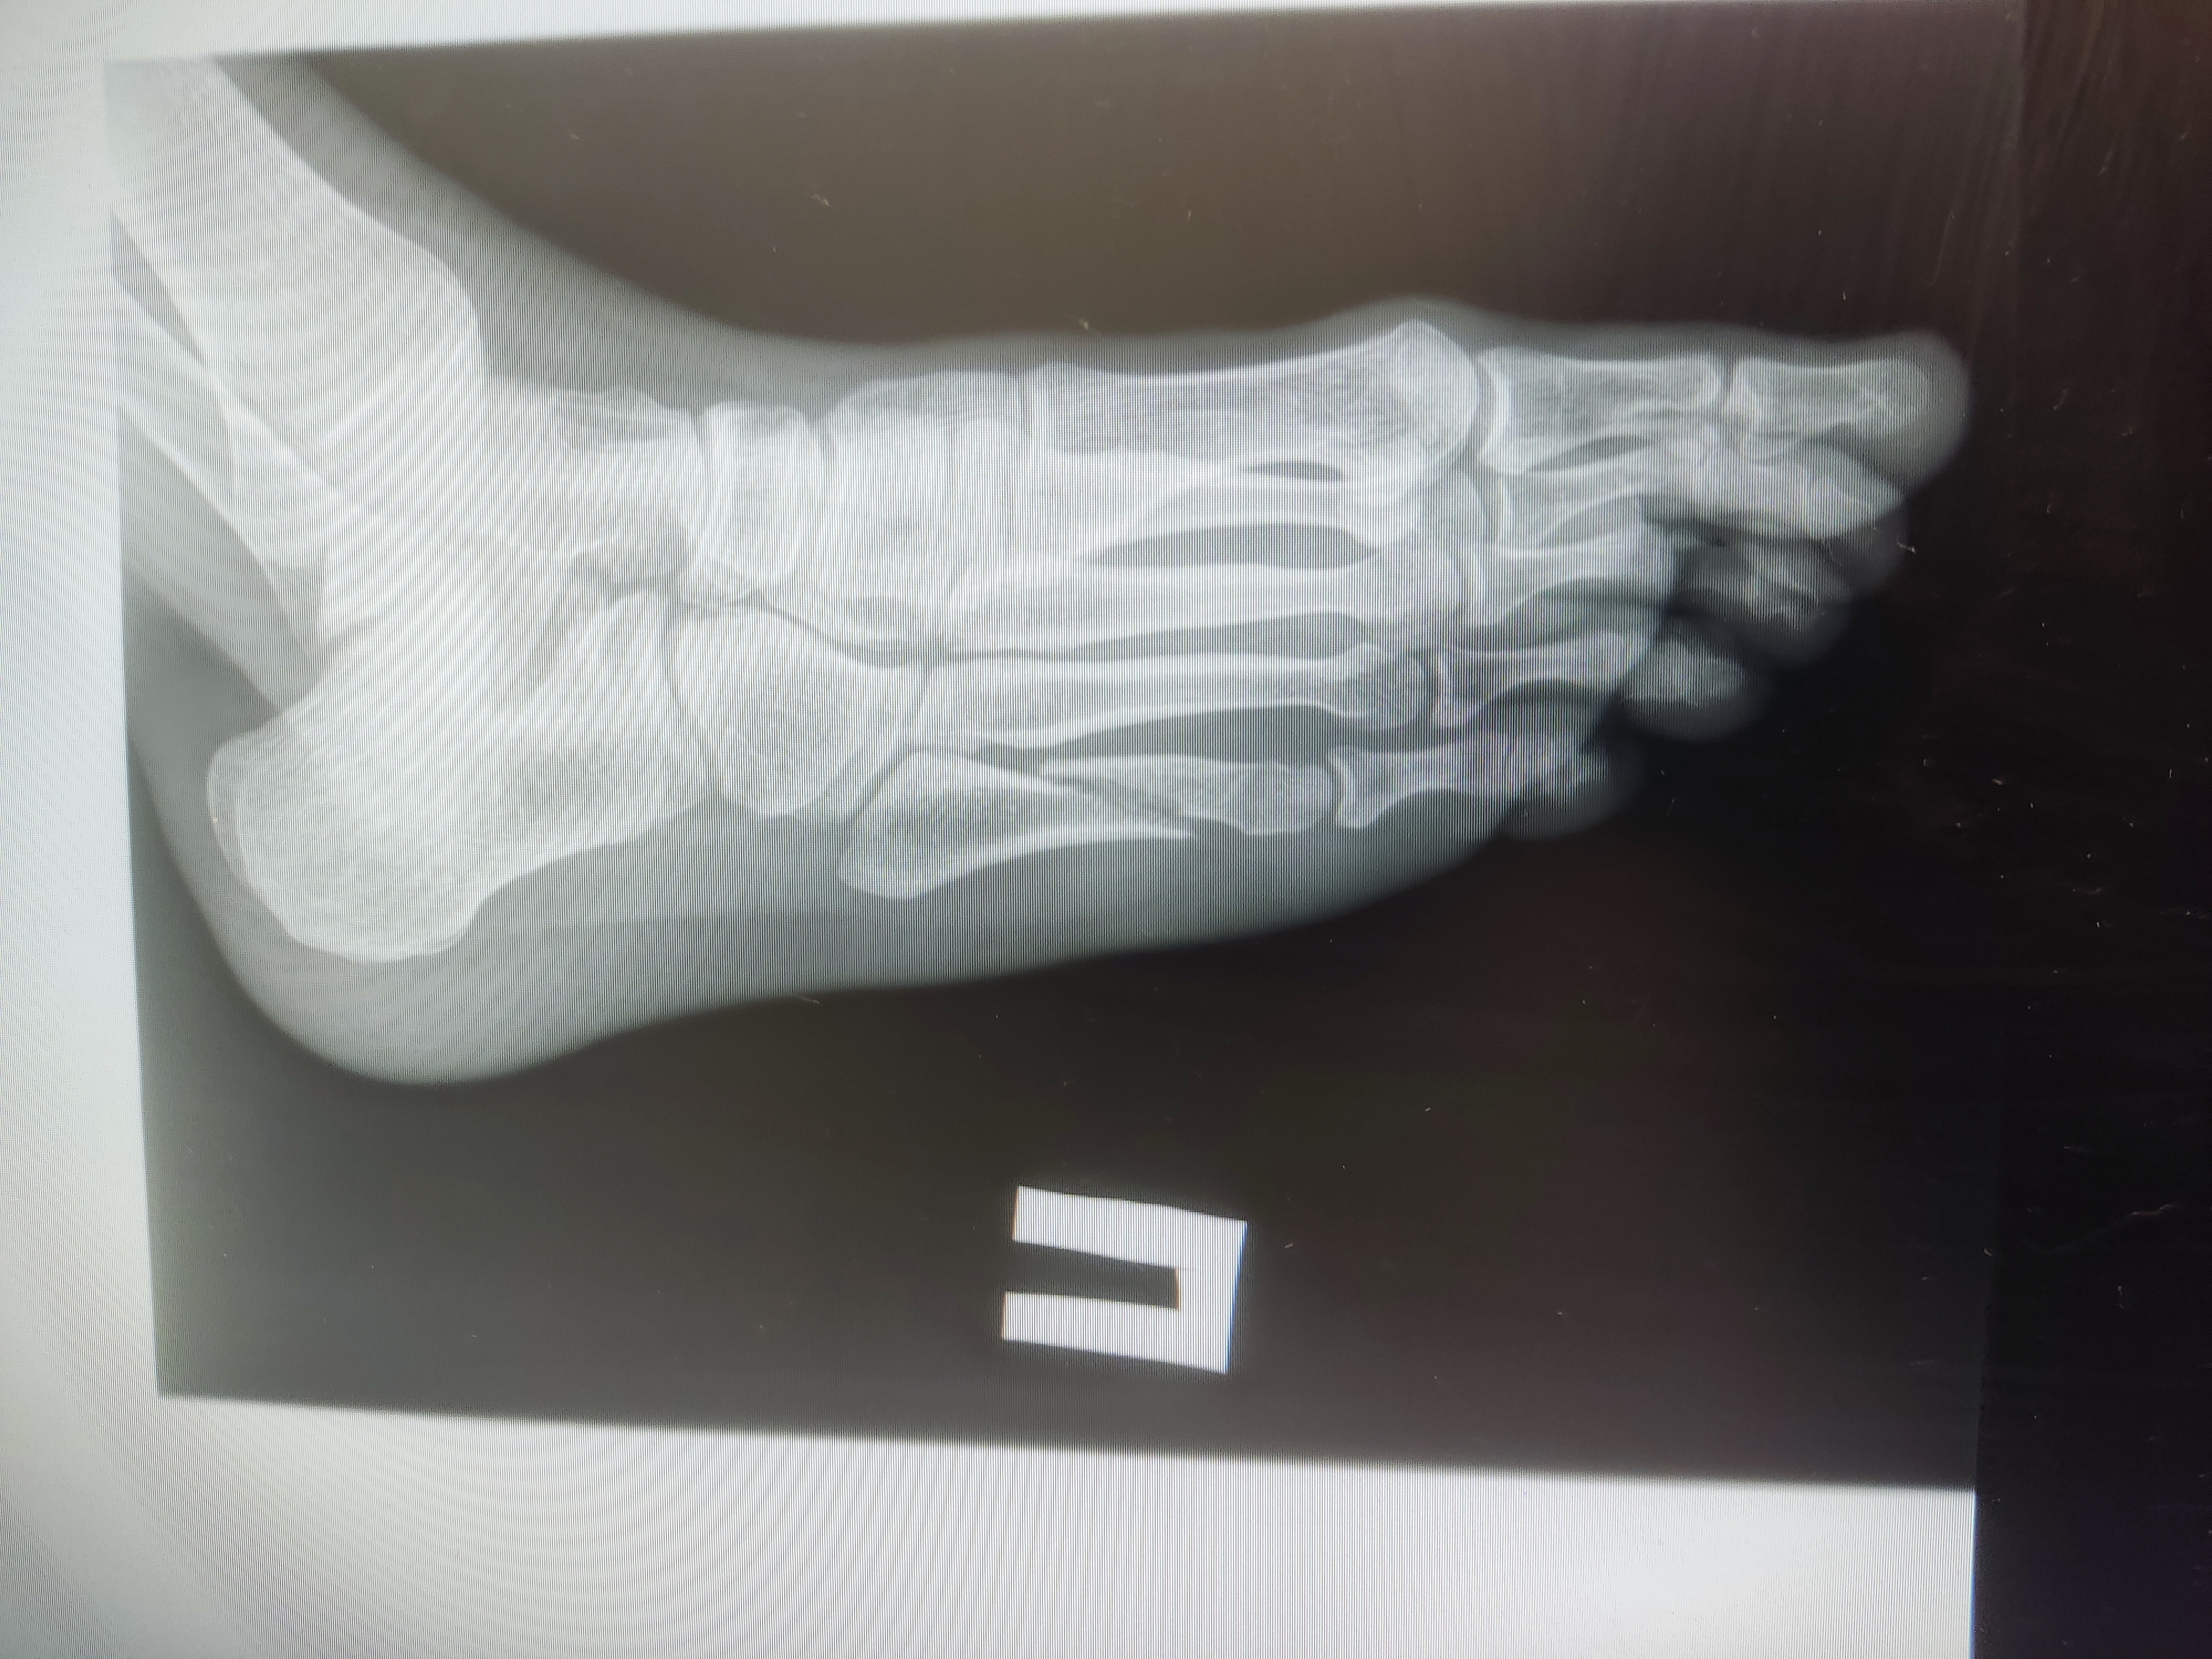

>>1651107

Гипс сняли на 4 неделю писал прошлый пост без гипса уже, в день его снятия

Вчерашние снимки выглядят так, тут уже 5 недель с момента перелома

>>1651121

мазоль уже образуется. не так быстро как хотелось бы, но все же. смещение умеренное. все будет хорошо.

>>1651610

Спасибо, анончик, обнадёжил

Последний снимок в прошлую пятницу назад по описанию показал 40% сращения, сказали, что можно неспеша ходить полноценно (а не с упором на пятку), продолжаю физио, назначили лфк и через две недели на работу. Со следующей недели начну передвигаться вне дома без трости

Итого 7 недель больничного будет. Видимо компенсация себе же за 7 лет без больничного

Полноценные длинные прогулки (от часа без перерыва) скорее всего буду вводить не раньше февраля (на третий месяц после перелома). Недавно гулял с тростью около получаса. Нога очень устала, в том числе передняя большеберцовая мышца. Мышцы за 5 недель ощутимо атрофировались, по всей видимости

Банально отвык ходить видать